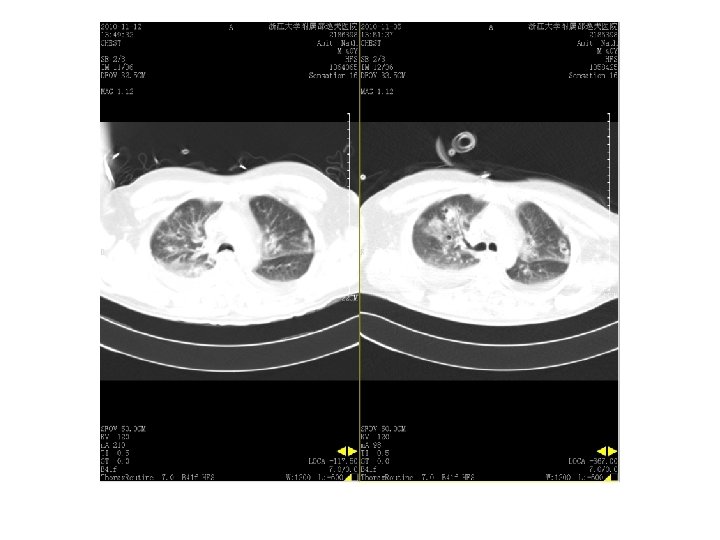

11. 12 vs 11. 5

2010. 9. 13复查CT